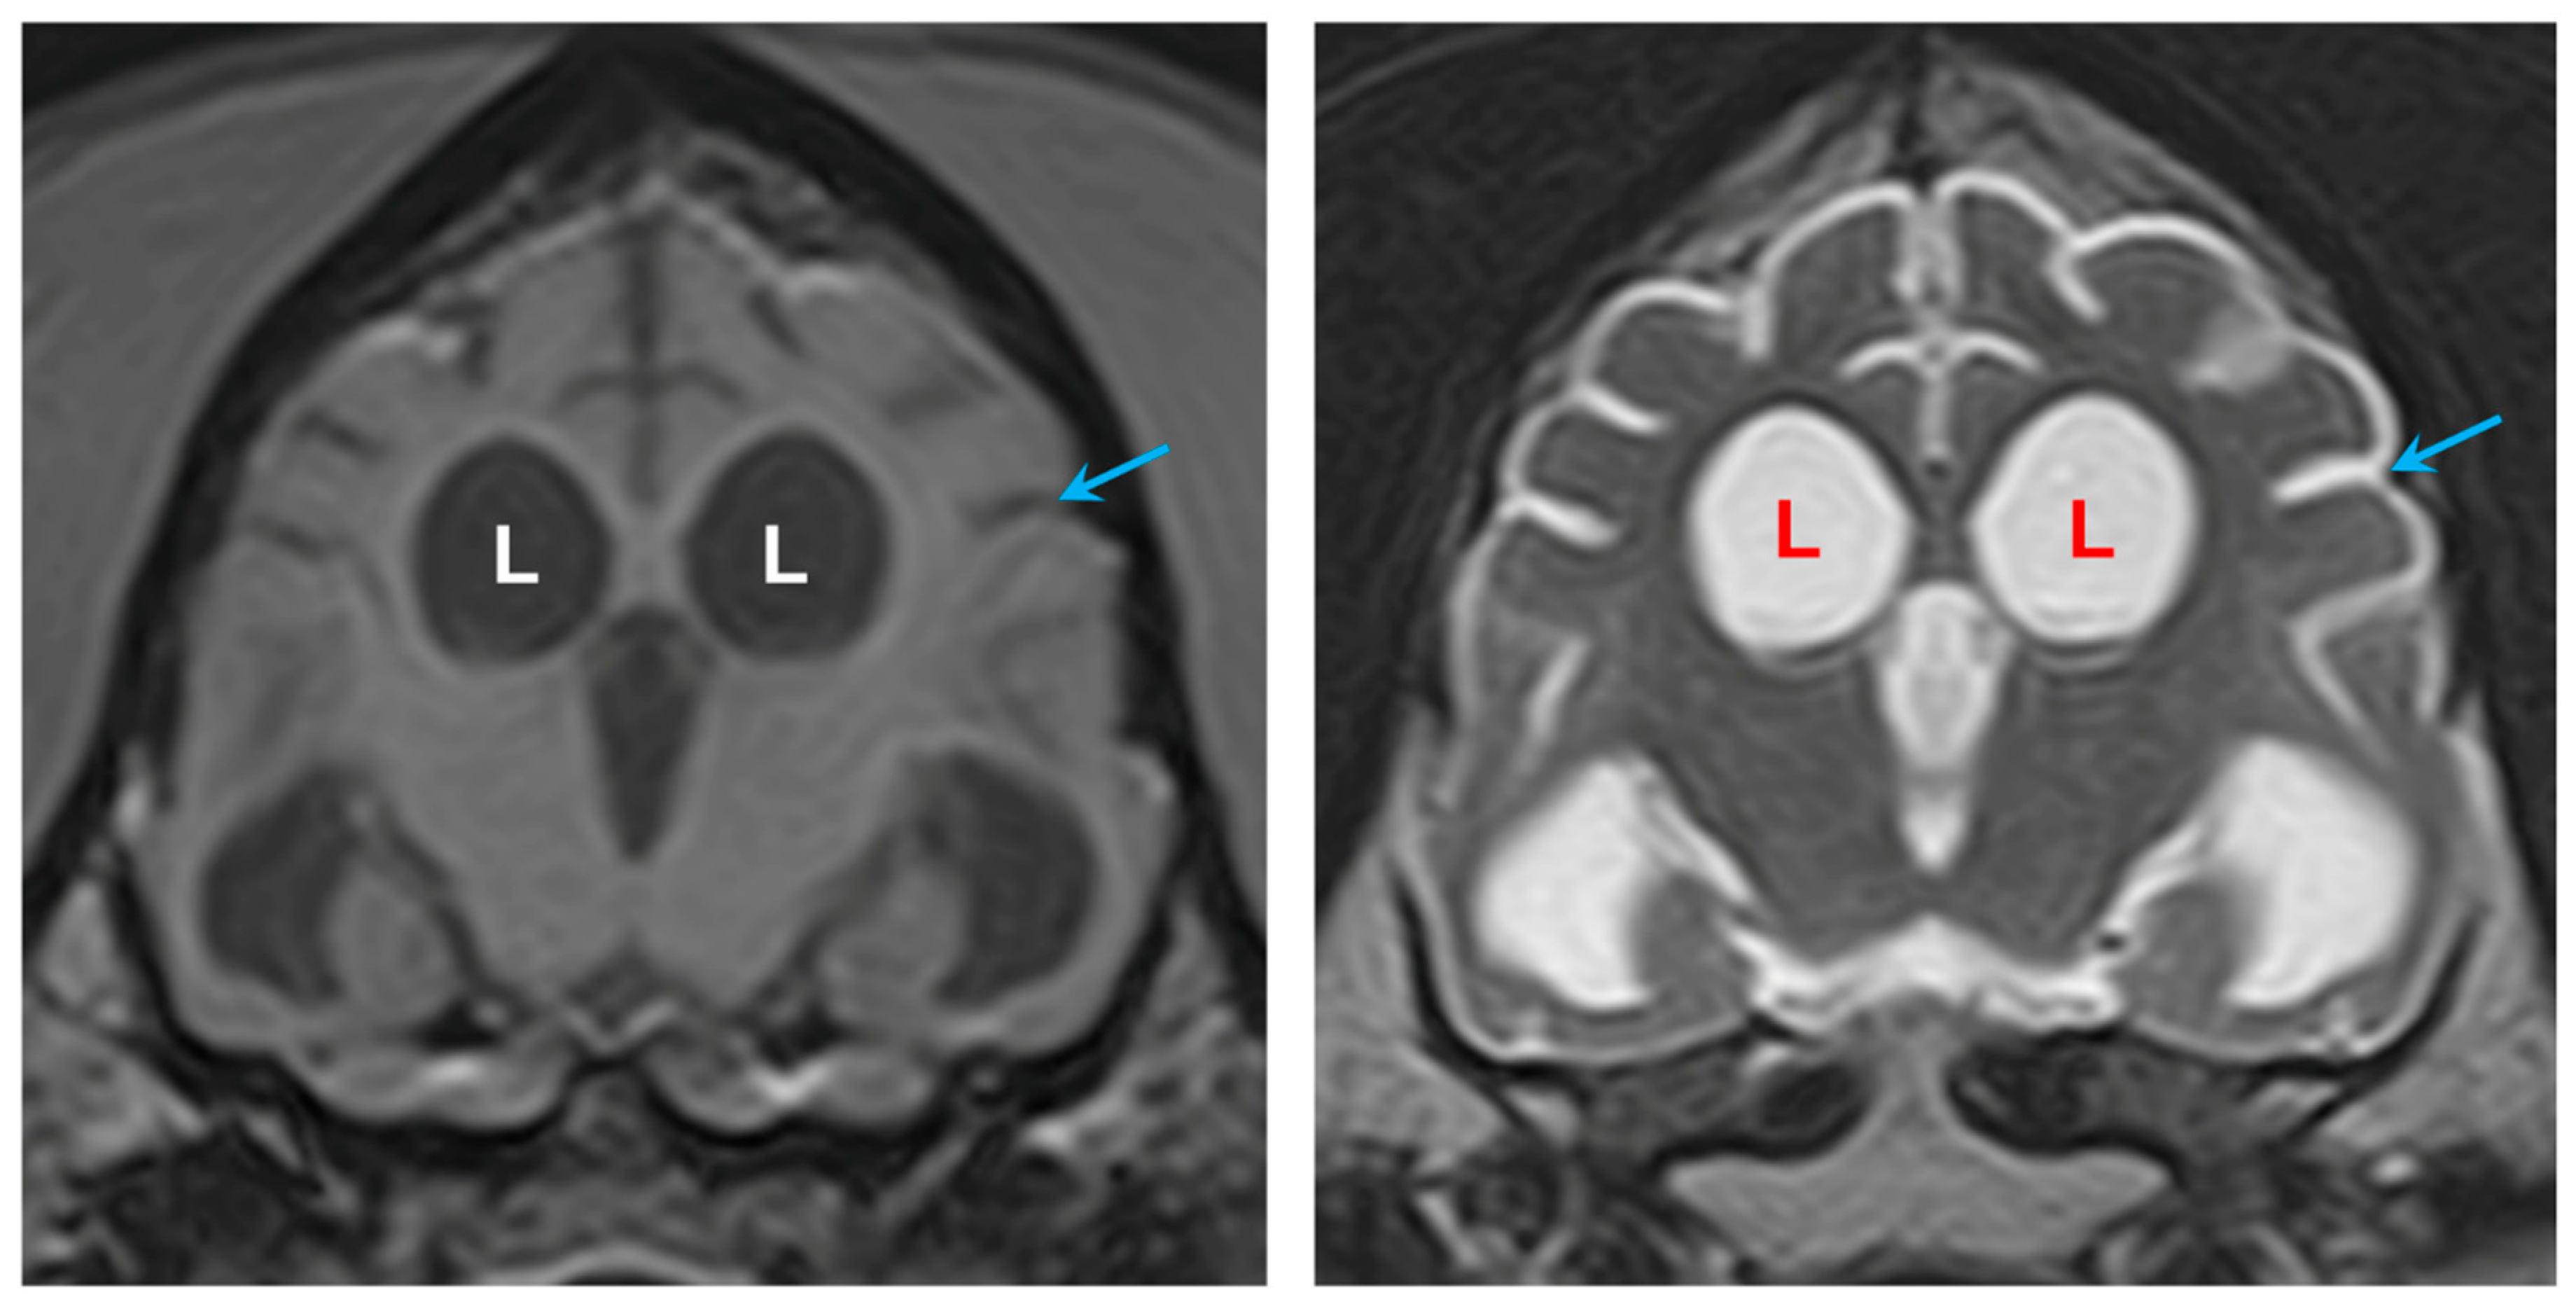

3.1. Disease Phenotype

3.2. Microscopic Findings